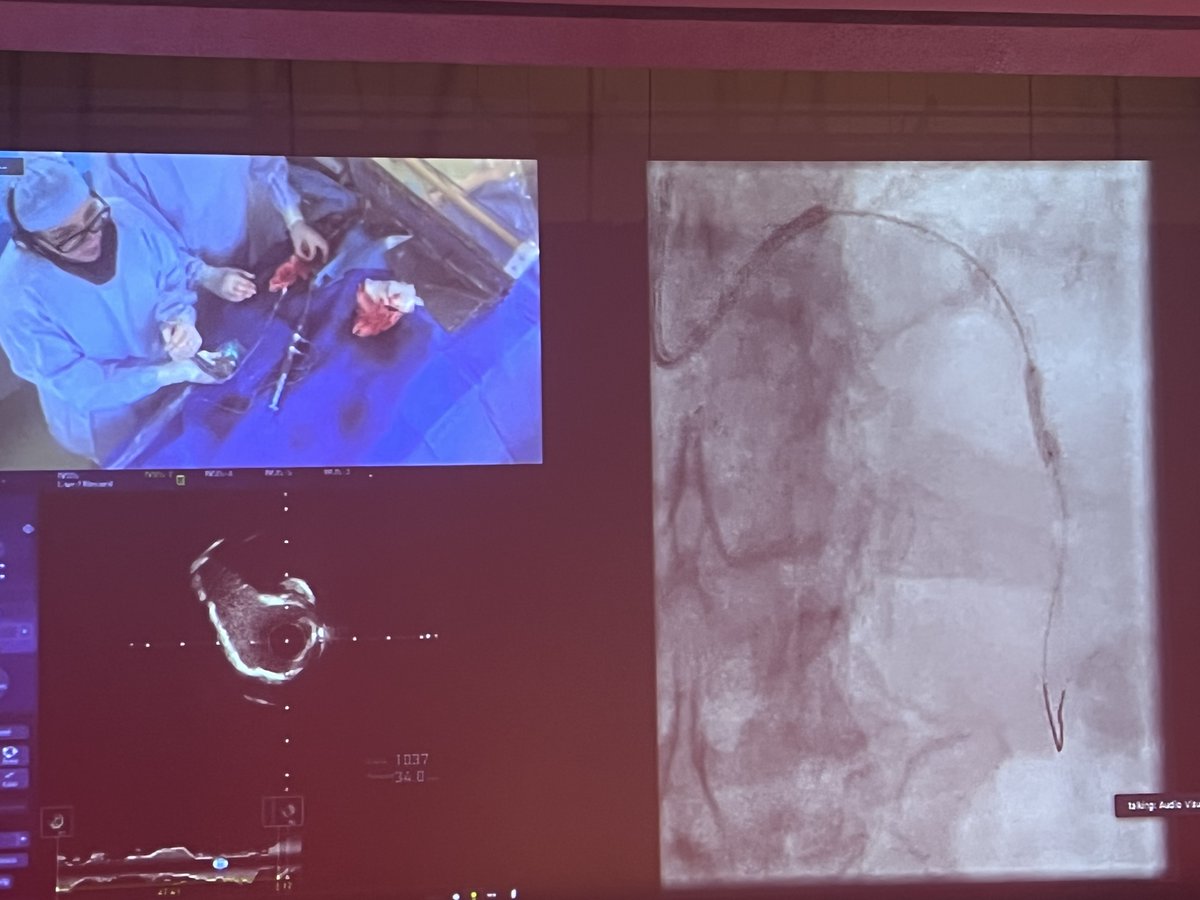

Great #RotaShock live case at #SIF2023 by Drs @AlokSharma081 @Herms2James @RizikMd & Richard Shlofmitz. Imaging with #OCT & #IVUS, @HonorHealth team used a 3.0 & 4.0 #ShockwaveC2 to treat concentric LAD Ca2+ & LM nodular Ca2+ for an excellent result! ISI bit.ly/3iEq7fc

ShockwaveIVL's tweet image. Great #RotaShock live case at #SIF2023 by Drs @AlokSharma081 @Herms2James @RizikMd & Richard Shlofmitz. Imaging with #OCT & #IVUS, @HonorHealth team used a 3.0 & 4.0 #ShockwaveC2 to treat concentric LAD Ca2+ & LM nodular Ca2+ for an excellent result!